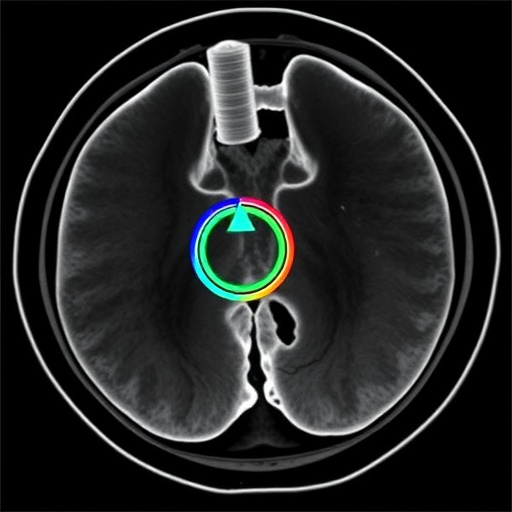

MRI-Steered Concentric Tube Catheter Enables Precise Interventions